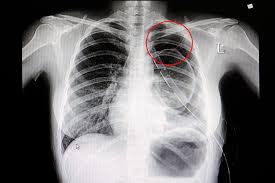

Diagnosis

Ask your patient about his/her history of lung disease and perform a physical exam. Measure the level of certain gases in patient’s bloodstream by lab blood tests.

Advise chest X-ray, sometimes it’s necessary to advise a CT scan or ultrasound.